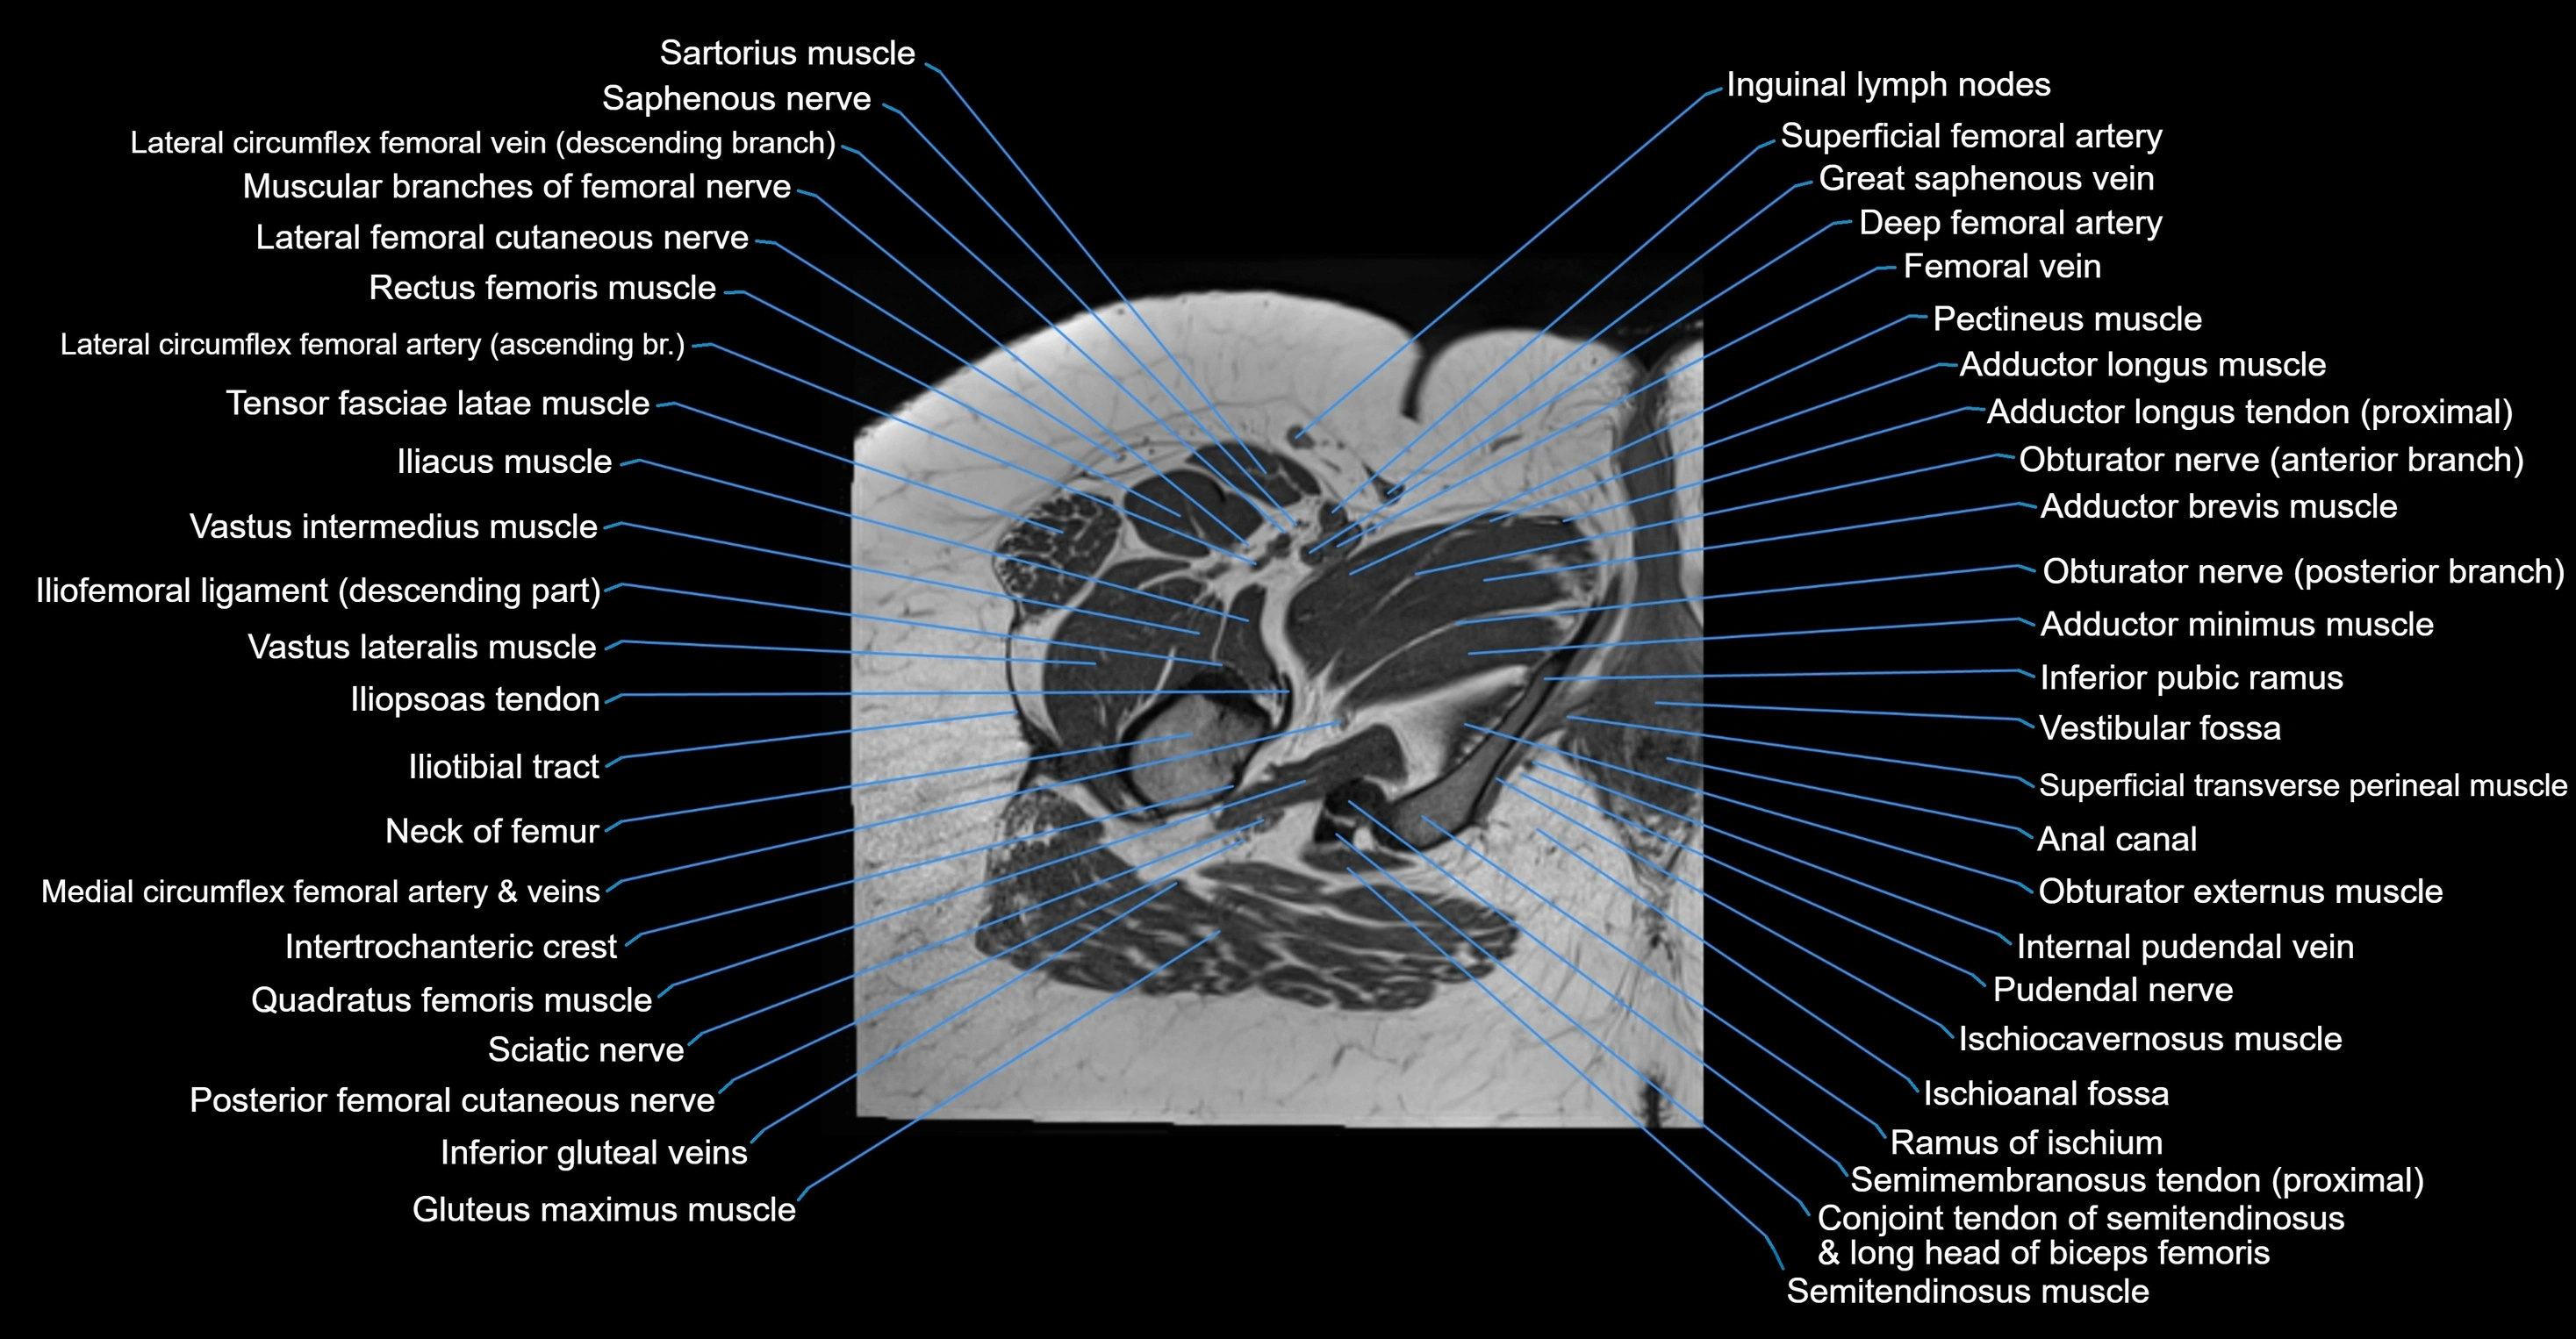

- Adductor brevis muscle

- Adductor longus muscle

- Adductor minimus muscle

- Anal canal

- Conjoint tendon of biceps femoris & semitendinosus

- Gluteus maximus muscle

- Iliotibial tract

- Inferior pubic ramus

- Intertrochanteric crest

- Ischiocavernosus muscle (Female)

- Neck of femur

- Obturator externus muscle

- Obturator nerve

- Posterior femoral cutaneous nerve

- Pudendal nerve

- Quadratus femoris muscle

- Ramus of ischium

- Saphenous nerve

- Sartorius muscle

- Semimembranosus tendon (proximal)

- Superficial transverse perineal muscle

- Vestibular fossa